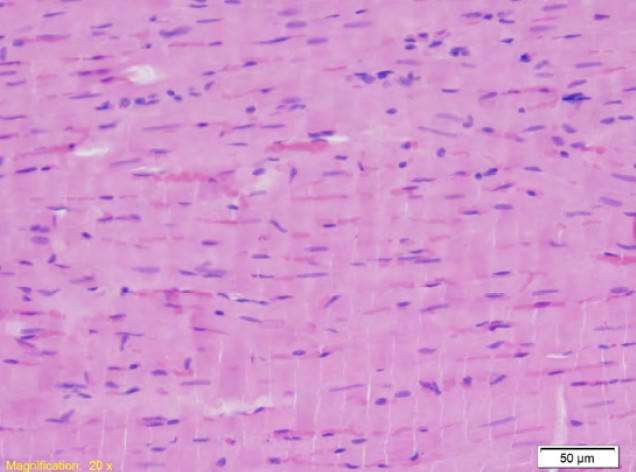

An assessment of cardiac histopathological changes in doxorubicin dose-dependent animal models

Rijad Jahić, Edina Lazović Salčin, Muhamed Katica, Almir Fajkić